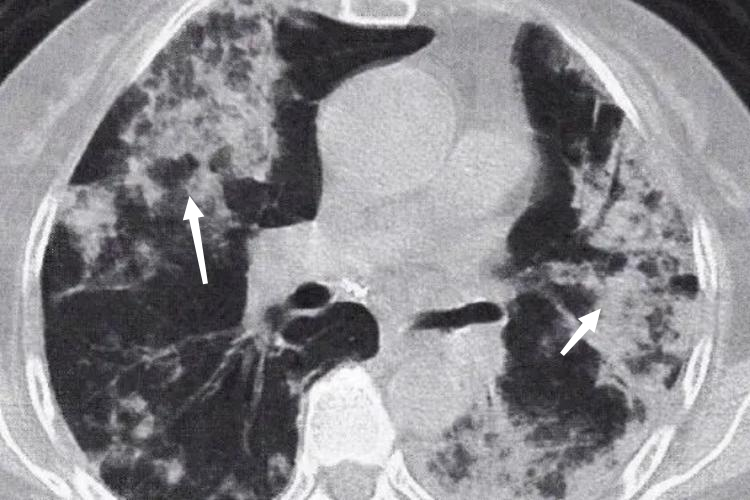

弥漫型:CT可见两肺弥漫分布的结节影,可伴有肺门、纵隔淋巴结增大。病变融合成大片肺炎实变影,其内可见“空气支气管征”,但其走行僵硬,呈“枯树枝样”改变。